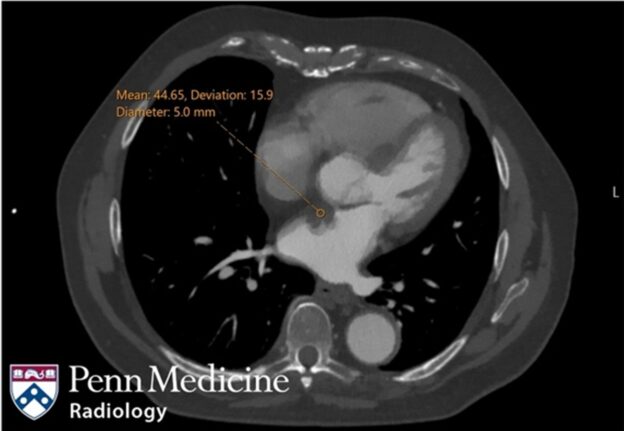

80-year-old man with ascending aortic aneurysm

An 80-year-old man presented for screening CTA chest for known ascending aortic aneurysm.